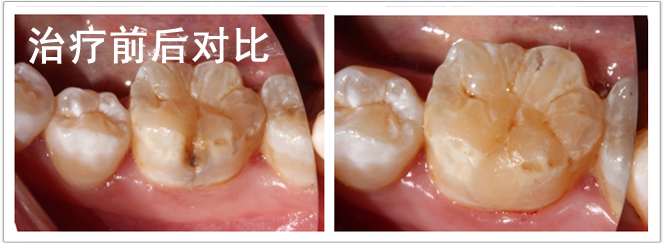

检查:颌面部未见异常,口内查:46颊面沟龋坏达牙本质层,温度测试正常。

诊断:46中龋

治疗计划:护充

治疗过程:46.去腐备洞 ,隔湿干燥,光照玻璃离子垫底,纳米充填, 调合,抛光。